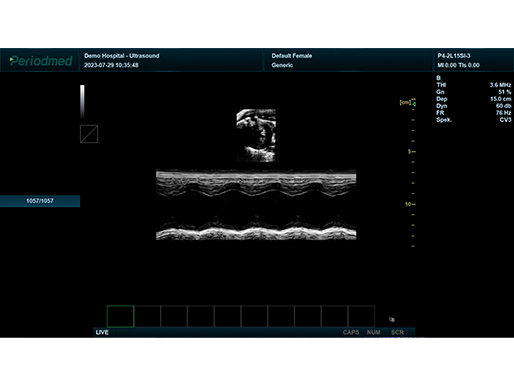

微凸探头-M模式-心脏 鼠

| 彩色M型、解剖M型 | |